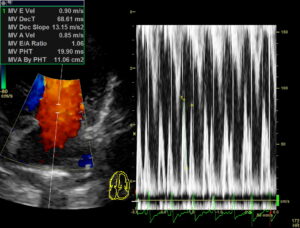

エコー(超音波)検査

エコー検査では様々な評価を行います。

雑音が聴こえる原因を探したり、重症度を評価したりします。

エコー検査はおよそ15分~30分で完了します。初めての検査の際は時間がかかる事もあるため、お昼の時間にお預かりして検査させていただきます。検査には特に麻酔などは必要ありません。

僧帽弁閉鎖不全症の治療開始の目安となるACVIMのステージ分類(A~Dまで)はレントゲン検査とエコー検査を組み合わせて評価します。

現在は、Stage B-2から治療を開始することが一般的となっています。